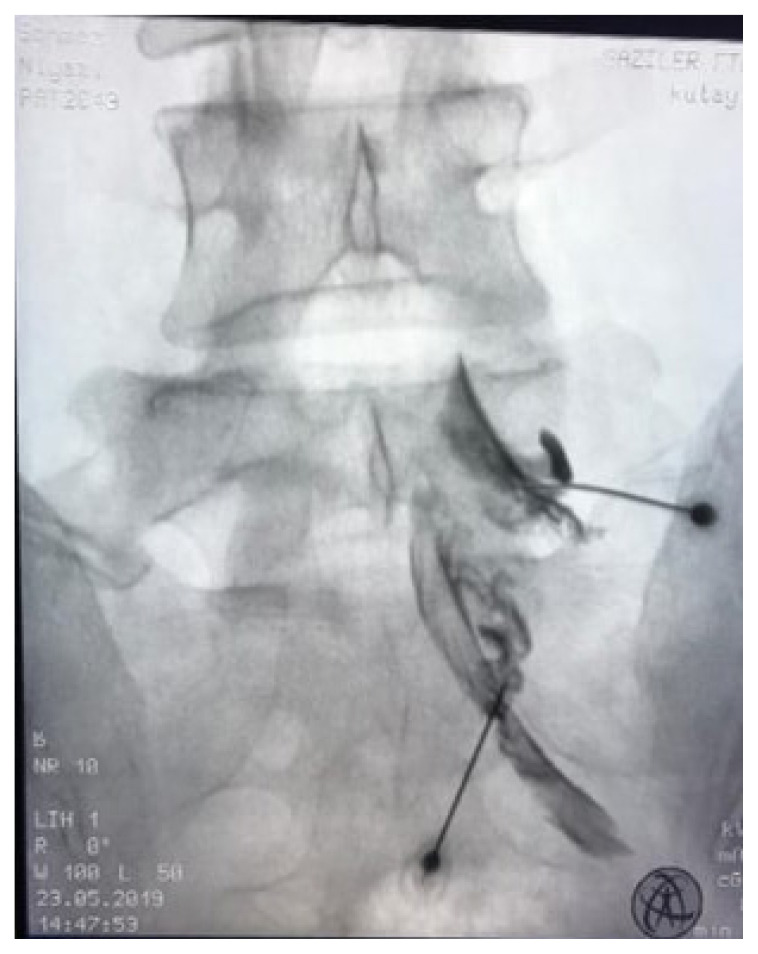

Materials and methods: A total of 50 patients were randomly divided into 2 groups of 25 patients each underwent PFOI by USG or TFESI via fluoroscopy. Pain intensity was assessed with visual analogue score (VAS), disability with Oswestry disability index (ODI), and QoL with short form-36 (SF-36), before treatment, at the 2nd week, 1st month, and 2nd month, after treatment.

Abstract Image